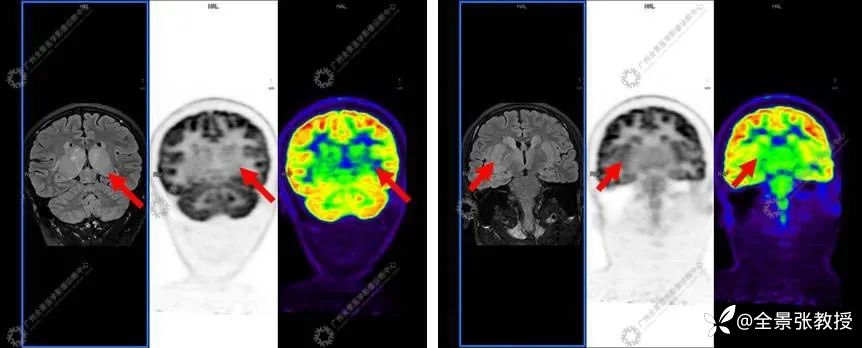

显示:双侧尾状核头-体部、双侧豆状核、双侧丘脑-漏斗-垂体柄、双侧颞叶海马-海马旁回可见对称性异常信号,T1WI呈稍低信号,T2WI及T2W-FLAIR呈稍高信号,DWI大部分呈等信号,右侧丘脑见小片状弥散轻度受限区,SWI未见出血信号;双侧丘脑肿胀,体积增大;MR波谱成像示双侧背侧丘脑NAA峰明显减低,Cho峰升高;双侧尾状核、豆状核各峰尚可,上述部位MR灌注减低,相应脑区FDG摄取对称性弥漫性减低,SUVave为2.92,其中右侧丘脑后缘见小条片状FDG摄取稍高,SUVmax为6.23。

诊断结果为:双侧尾状核头-体部、双侧豆状核、双侧丘脑-漏斗-垂体柄、双侧颞叶海马-海马旁回对称性异常信号,且MRI灌注及糖代谢弥漫性明显减低,提示局部脑功能受损明显;双侧丘脑肿胀;颅脑MRI波谱示病变区NAA峰明显减低,Cho峰升高,提示相应部位神经元受损;考虑中枢系统恶性肿瘤,弥漫性中线胶质瘤可能。后病理证实为H3K27M突变型弥漫性中线胶质瘤。